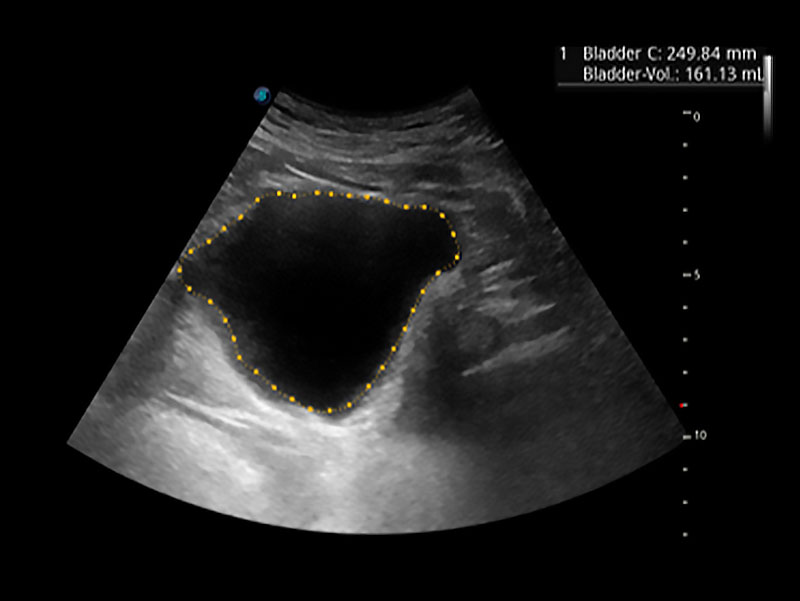

一鍵自動識別膀胱壁及自動測量膀胱容積,不受膀胱形狀和大小的限制,幫助醫(yī)生快速精準(zhǔn)獲得測量的數(shù)據(jù)。